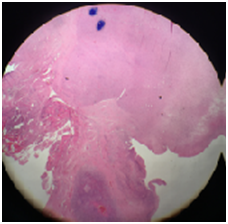

In fact our case present with chronic tonsillitis, SOB, cough and weight loss. On examination there was unilateral tonsillar hypertrophy and slough. Tonsillectomy was done then followed by histopathology investigation which shows Figure 1-4: Right tonsil reveal caseating granuloma and zeihl-neelsen stain shows AFB positive. Left tonsil reveal smooth muscle tumor consistent with leiomyosarcoma. Our patient was subsidiary finding HIV +ve. We need further studies to recognize accurately the mechanism behind this interesting case and other cases as well. We would put a query concerning this case: - is there any relation between TB patient who have HIV +ve and leiomyosarcomas?

Pathological Figures (1-4) Fascicles of spindle cells with mild to moderate atypia, surface necrosis and ulceration. Mitotic, mitosis/10 high power field.